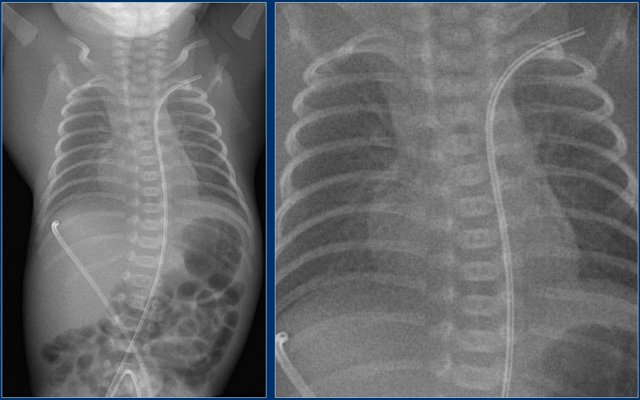

Umbilical artery line (3)

First study the images.

Then continue reading.

The findings are:

1. Malposition of umbilical artery line, folded in the abdominal aorta.

Umbilical artery line (4)

1. Deep position of umbilical artery line, in aortic arch.

2. Umbilical vein line with tip in right portal vein.